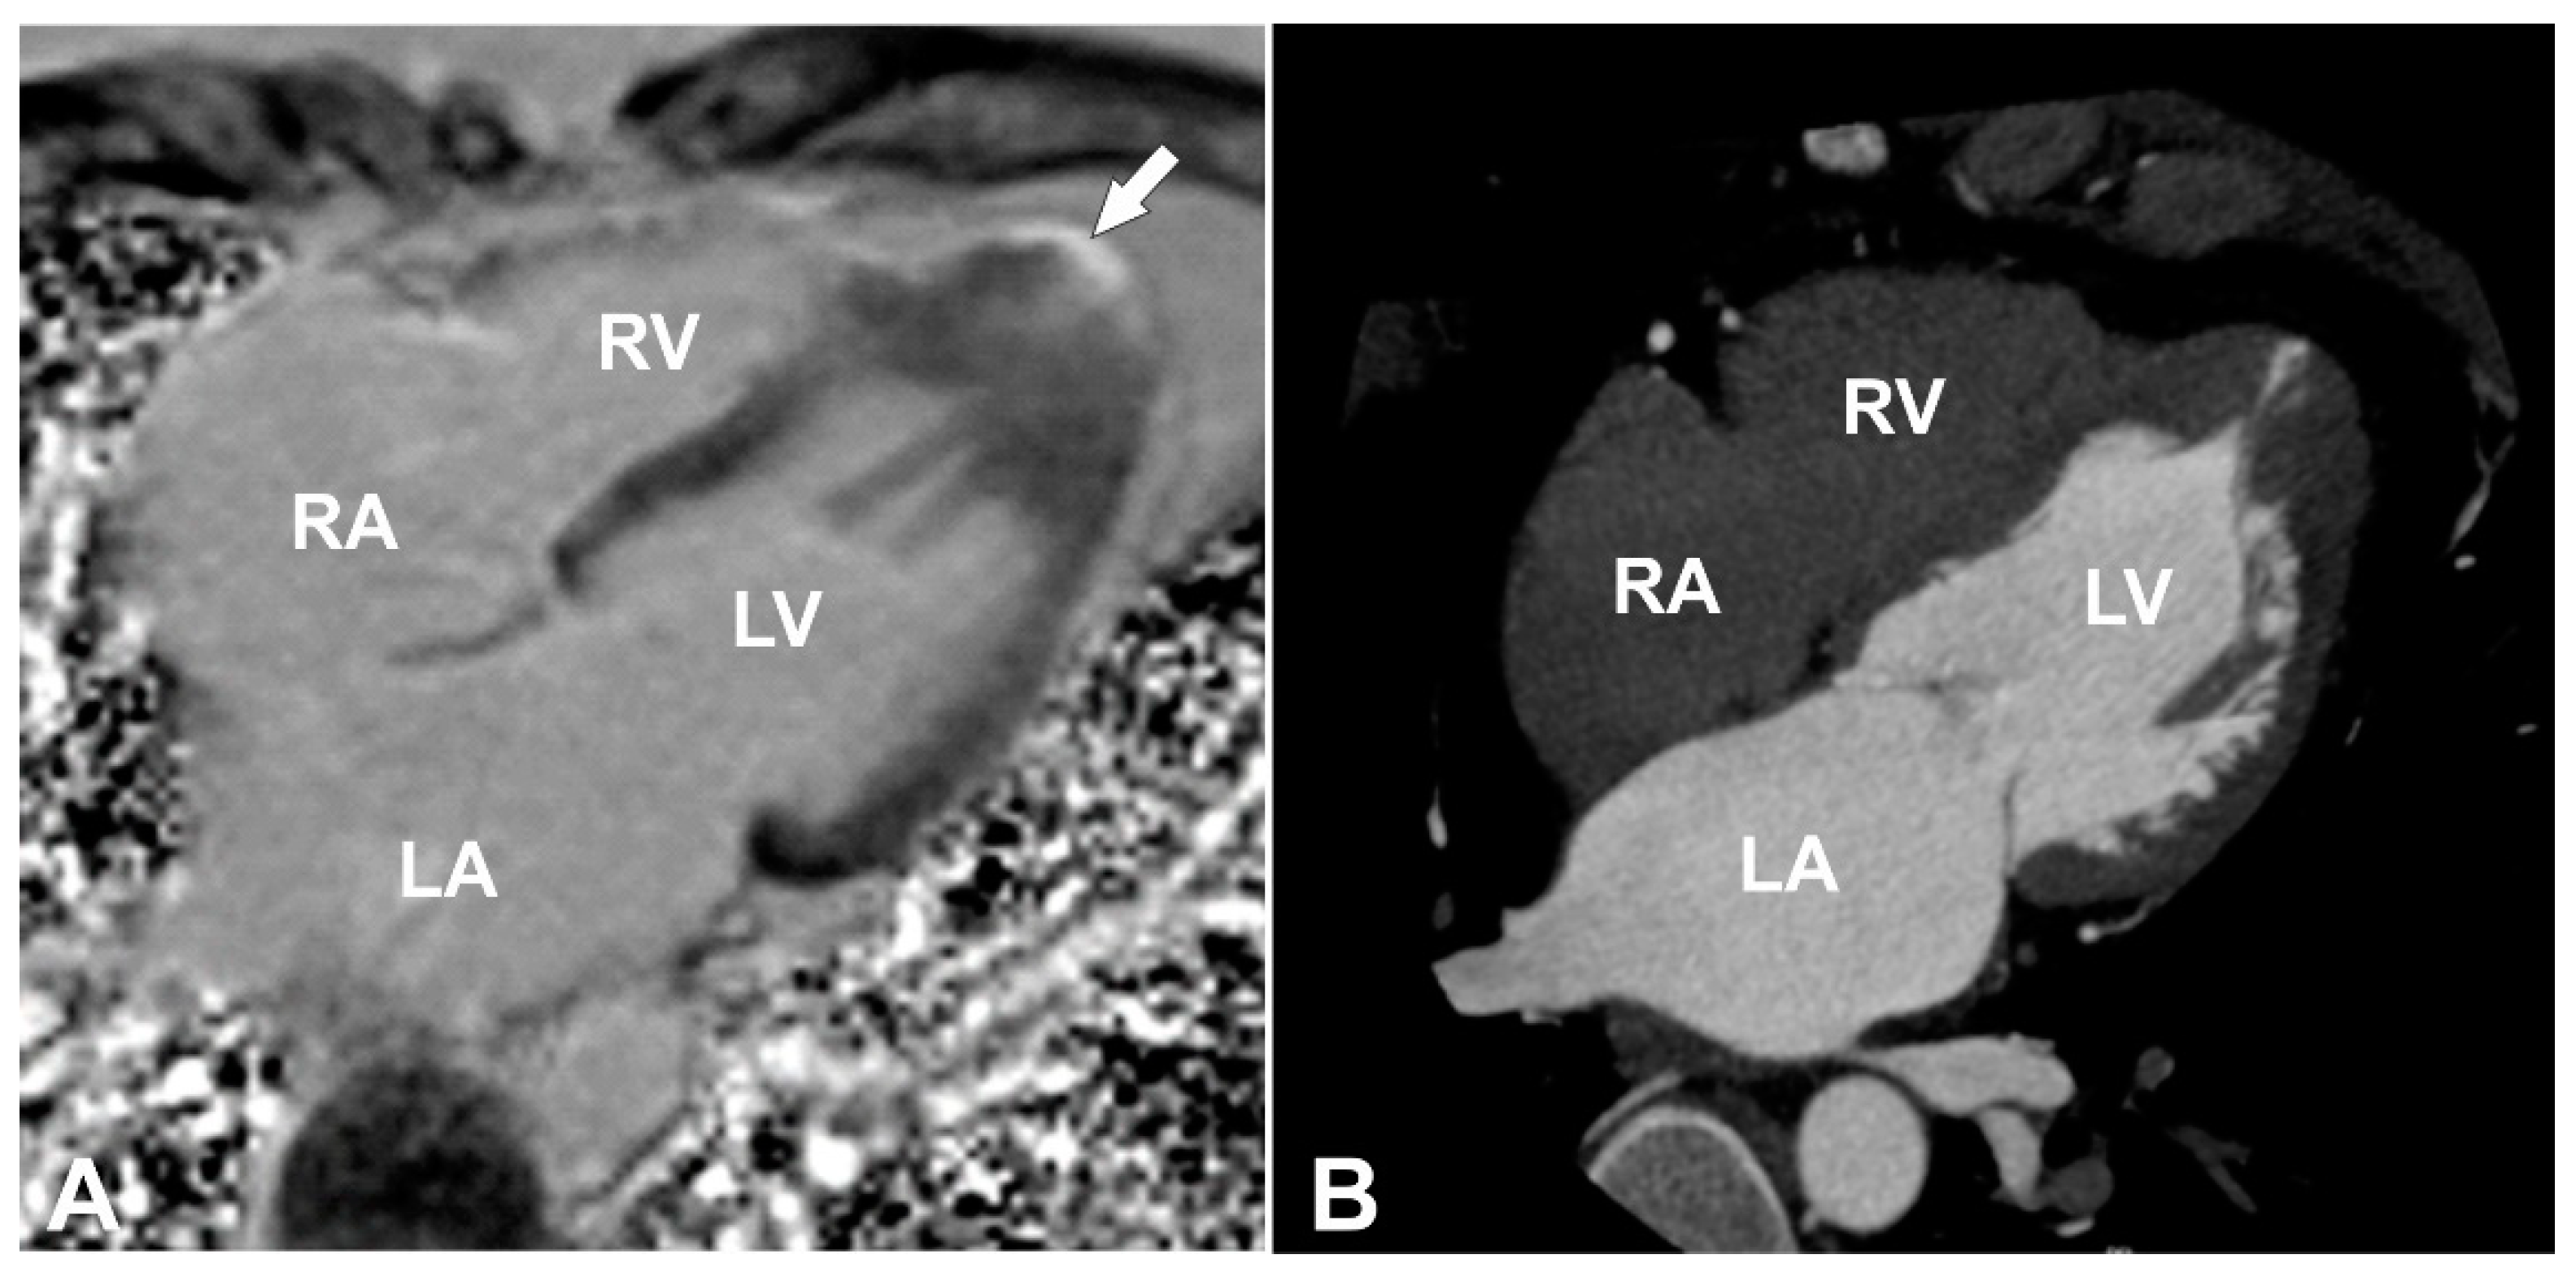

A 39-year-old male consulted a cardiologist on an outpatient basis due to nonanginal chest pain episodes five years ago and was diagnosed with isolated apical HCM by using TTE. At the time of follow-up consultation, the patient was asymptomatic with an unremarkable personal history and a family history of unspecified congenital heart disease and sudden cardiac death of his sister and his aunt. His physical examination was without any pathological findings. Electrocardiogram showed sinus rhythm, 80 bpm, hypertrophy of left ventricle (LV), and deep negative T-waves in leads I, aVL, V4–6. Blood biochemistry was normal. TTE was performed and demonstrated isolated apical HCM with apical micro-aneurysm. Interestingly, blood flow was registered in the projection of hypertrophied midventricular segments, raising the question about the correctness of the previous diagnosis. CMR was scheduled for clarification of the heart’s morphology and function, as well as for additional risk stratification of the patient. The CMR revealed hyperkinetic LV with a hyperkinetic ejection fraction around 84% and overlapping phenotypical pattern of LV myocardium with hypertrophy of compacted apical segments (maximum wall thickness up to 16 mm (Figure 1E,F) and hypertrabeculation of midventricular segments with a ratio of non-compacted and compacted myocardium up to 2.8 at end-diastole (Figure 1C,D; Supplementary Videos S1–S5). Additionally, LV apical micro-aneurysm (Figure 1A,B) was detected with transmural late gadolinium enhancement (LGE) in its wall, showing transmural fibrotic changes (Figure 2A). To exclude any coronary artery anomalies or underlying coronary artery disease coronary, computed tomography (CT) angiography was performed which demonstrated normal coronary arteries without any atherosclerotic changes or anomalies with morphological changes of LV consistent with the CMR findings (Figure 2B). Then, 24 h ECG monitoring was performed and revealed four sporadic ventricular premature beats.

The overlapping phenotype in the adult patient described was diagnosed based on the established diagnostic criteria of both CM. The best imaging modality to prove phenotypical features is definitely CMR imaging. In our adult patient, HCM was diagnosed based on the European Society of Cardiology (ESC) guidelines for the diagnosis and management of HCM. In the latter guidelines, HCM is defined by a wall thickness ≥15 mm in one or more LV myocardial segments—as measured by any imaging technique (echocardiography, CMR or CT)—which is not explained solely by loading conditions [2]. In our patient, apical segments proximal to the apical microaneurysm were measured to be up to 16 mm in diastole, which is consistent with diagnostic criteria for HCM (Figure 1A,B,E,F). Additionally, next to the hypertrophied compact part of LV, we noticed a noncompaction area, which was more prominent at the level of midventricular segments. In order to diagnose noncompaction, we used the CMR criteria proposed by Petersen et al. [13]. Using the latter criteria, a diastolic non-compacted to compacted ratio >2.3 identifies pathological noncompaction with values for sensitivity, specificity, and positive and negative predictions of 86%, 99%, 75%, and 99%, respectively. Thus, a diastolic non-compacted to compacted myocardial ratio equal to 2.8 was consistent with the diagnosis of left ventricular noncompaction at the level of midventricular segments (Figure 1C,D). Taking into account two phenotypical features in our patient, we considered our patient to have an overlapping hypertrophic and noncompaction phenotype.

Figure 2. (A) Magnetic resonance four chamber heart view obtained with inversion recovery sequence 10 min after injection of gadolinium-based contrast agent (late gadolinium enhancement (LGE) image) with apical fibrotic changes denoted with a white arrow. (B) Four-chamber computed tomography heart view representing the morphologic findings of the heart seen on magnetic resonance images. LA—left atrium; LV—left ventricle; RA—right atrium; RV—right ventricle.